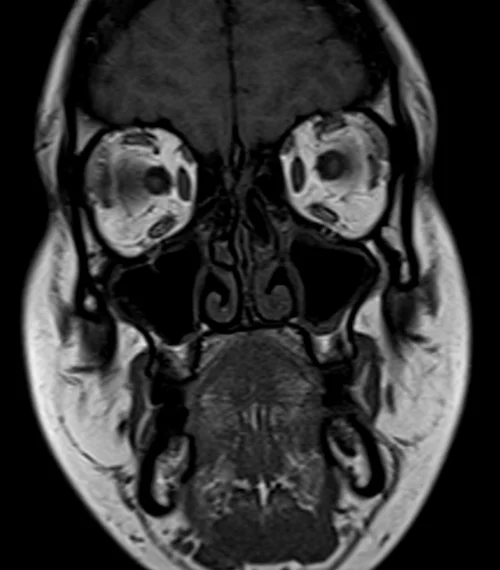

Orbits

BRAIN ORBITS